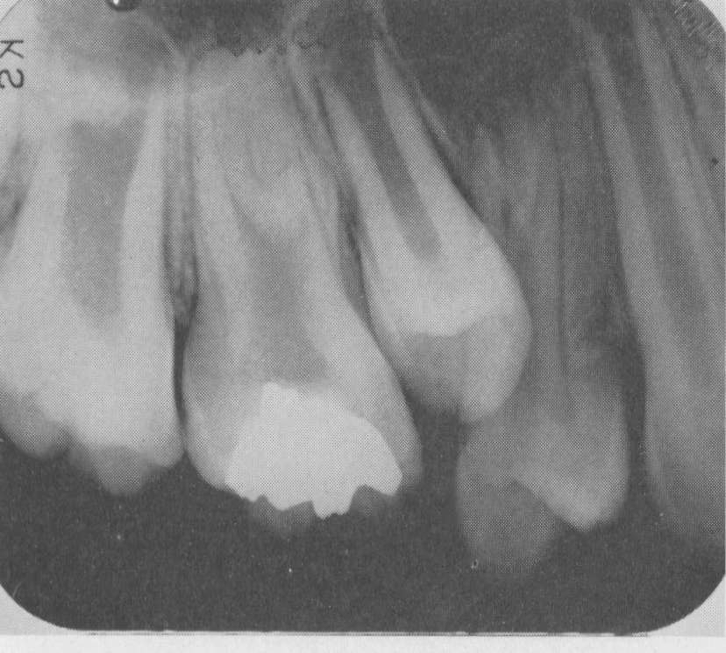

Dens in dente